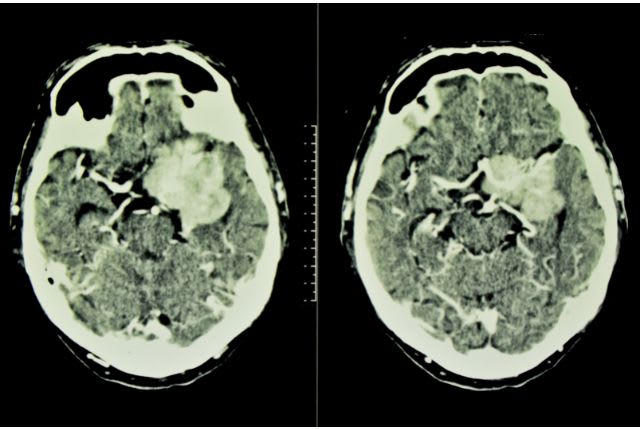

Comment diagnostiquer un méningiome : IRM, scanner, PET-Scan ?

L’IRM (Imagerie par Résonance Magnétique) est l’examen de référence pour le diagnostic du méningiome ; celui-ci est réalisé généralement en injectant au patient un produit de contraste afin de bien visualiser les structures du cerveau et des méninges. D’autres examens d’imagerie médicale, comme le scanner ou le PET-Scan, peuvent également être envisagés pour étudier la localisation et la vascularisation du méningiome. Une biopsie cérébrale peut également être envisagée dans certains cas. D’autres examens, comme un bilan ophtalmique, un électroencéphalogramme ou encore un bilan neuropsychologique peuvent enfin compléter le diagnostic (notamment si une intervention est envisagée).